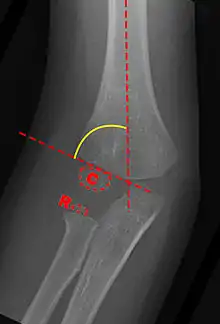

Carrying angle can be evaluated through AP view of the elbow by looking at the Baumann's angle.[3] There are two definitions of Bowmann's angle:

The first definition of Baumann's angle is an angle between a line parallel to the longitudinal axis of the humeral shaft and a line drawn along the lateral epicondyle.

Another definition of Baumann's angle is also known as the humeral-capitellar angle. It is the angle between the line perpendicular to the long axis of the humerus and the growth plate of the lateral condyle. Reported normal values for Baumann's angle range between 9 and 26°.[7] An angle of more than 10° is regarded as acceptable.[7]